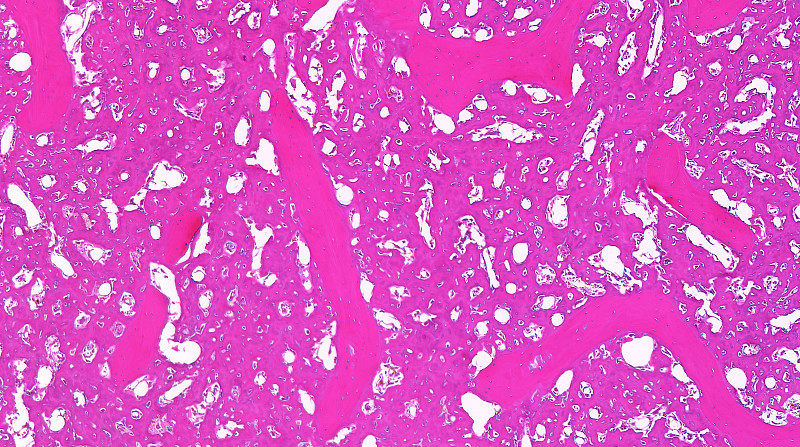

Nielsen 等[21] 报道了 PLD 联合 IFO 治疗晚期转移性软组织肉瘤的 I期临床研究,PLD 推荐剂量为30 mg/m2,其剂量限制毒性主要为骨髓抑制和过敏反应。EORTC 软组织和骨肉瘤组的一项Ⅱ 期临床试验显示,治疗晚期软组织肉瘤的 2 组患者中,一组使用PLD 50 mg/m2,每 4 周重复方案;另一组使用 ADM75 mg/ m2,每 3 周重复方案,2 组有效率差异无统计学意义,PLD 组严重不良反应发生率相对较低[22] 。基于以上报道,本研究选择 PLD 50 mg/m2用于骨肉瘤新辅助化疗,替代常规使用的 ADM 60~75 mg/m2,ADM 组和 PLD 组术后 Huvos 法检查肿瘤坏死率,坏死率≥90%病例分别为 47.3%和 50.0%,表明在骨肉瘤新辅助化疗中 PLD 50 mg/m2 替代 ADM 60~75 mg/m2在抗肿瘤活性方面等效。